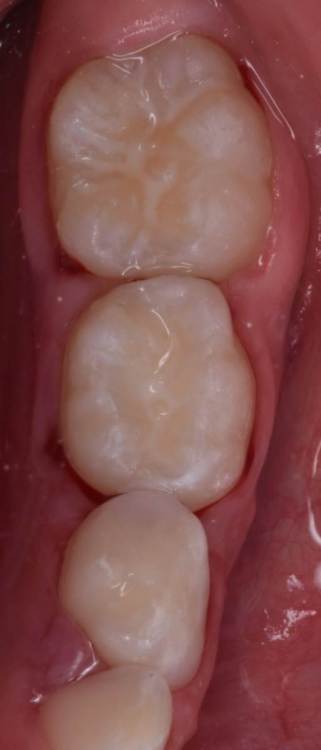

CRAZYDUCK Опубликовано 30 июня, 2022 Автор Поделиться Опубликовано 30 июня, 2022 Пример лечения обратимого пульпита 7.5 зуба . 2 1 Ссылка на комментарий